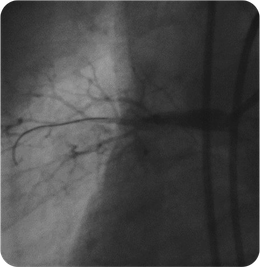

血管造影

左腸骨動脈が完全閉塞しており、左下肢の冷感、痛みを認めました。ステントを留置しいずれの症状も消失しています。